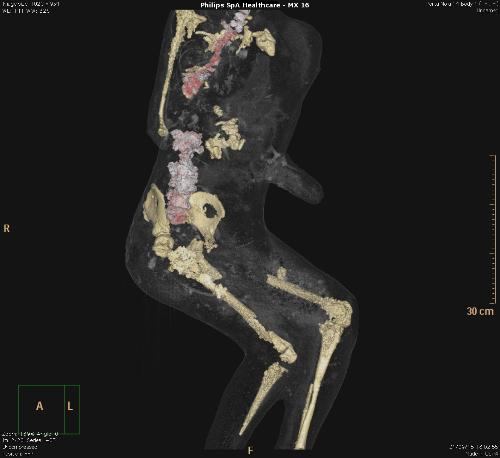

Por primera vez, un grupo de moldes de yeso de Pompeya ha sido sometido a tomografías axiales computerizadas (TAC), a partir de las que ha sido posible determinar la edad, las patologías médicas, los hábitos alimentarios y el estilo de vida de los habitantes de la ciudad arrasada por el Vesubio en el 79 d.C.

El objetivo del estudio radiológico ha sido obtener imágenes del interior de los cuerpos que quedaron conservados en ceniza durante la erupción del volcán, y que luego fueron rellenados con yeso con el propósito de preservar su integridad.

Asimismo, han sido realizados relieves en tres dimensiones de todos los cuerpos mediante técnicas digitales de vanguardia que permiten obtener datos sobre cómo ha variado su estado de conservación en el tiempo.